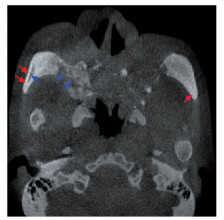

• 摘要: SAPHO综合征是一类以骨关节和皮肤病变为特点的罕见临床综合征,即出现滑膜炎(synovitis)、痤疮(acne)、脓疱病(pustulosis)、骨肥厚(hyperostosis)和骨炎(osteitis)等一系列病变。本文报道一例具有31年病史的非典型SAPHO综合征患者,经详细的诊断及鉴别诊断以及合理的诊疗方案的实施,最终患者病情获得明显改善。通过回顾并总结SAPHO综合征的临床诊疗特点,以及对该病例的讨论分析过程,充分体现了多学科诊疗在罕见病诊治中的有效性及必要性。

Abstract: The SAPHO syndrome is a rare disease characterized by osteoarticular and dermatological manifestations. Here we reported an atypical case of SAPHO syndrome for 31 years. A multidisciplinary team made the diagnosis and differential diagnosis of the patient's osteoarticular and dermatological lesions. Subse-quently, suitable treatment was initiated and the patient's condition was significantly improved. At last, we reviewed and sum- marized the characteristics of diagnosis and treatment of SAPHO syndrome. The effectiveness and necessity of multidisciplinary treatment were demonstrated by the discussion and analysis of this rare disease.